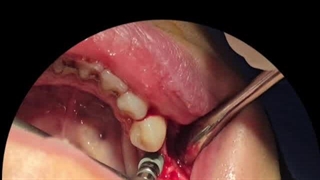

کاشت دندان تخصصی در میدان حر تهران مطب دکتر پورصادقی